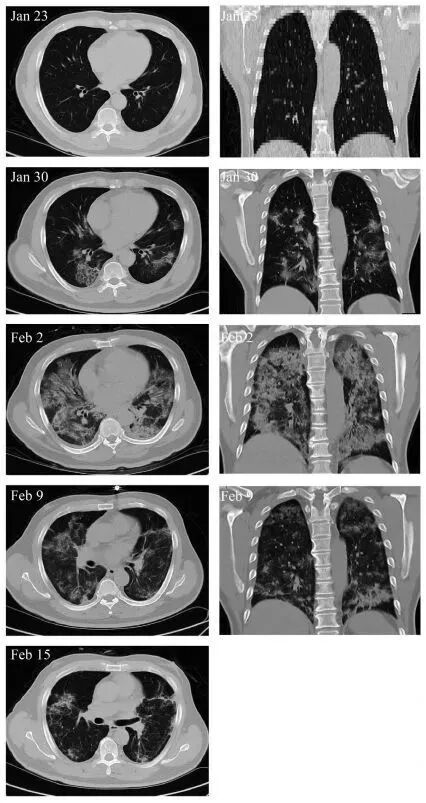

在2020年1月23日至2月16日期间,研究者共征集了7名COVID-19患者,其中包括1名危重症患者、4名重症患者和2名轻症患者,探究间充质干细胞治疗后14天内,患者的免疫系统和炎症系统功能变化,以及副作用的发生情况。

2月1日,患者血浆天冬氨酸转氨酶、肌酸激酶活性和肌红蛋白分别激增至57 U/L、513 U/L和138 ng/ml,表明肝脏和心脏遭受严重损害;但这些功能性生化指标的水平均在治疗后2?4天降至正常参考值,2月13日恢复至正常水平,分别为19 U/L,40 U/L和43 ng/ml。另外,MSC治疗能显著加快治疗进程。治疗后4天,新冠肺炎危重症患者呼吸频率降至正常范围、发烧和呼吸急促等症状消失。治疗后9天,胸部CT成像显示毛玻璃样混浊和肺炎浸润已大大减少。